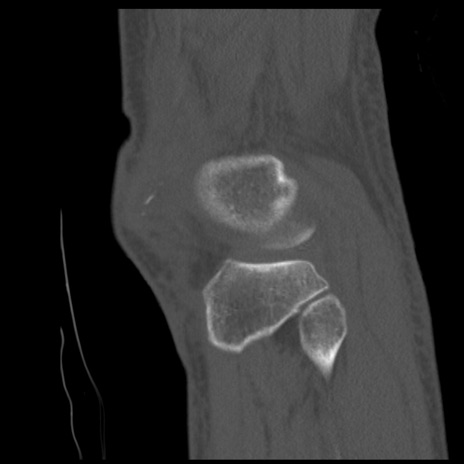

症例28 右膝関節CT(矢状断像)

右膝関節CT